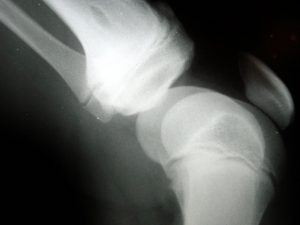

The knee is the largest joint in the body and it consists of collateral ligaments, cruciate ligaments and menisci. Damage to the kneecap, the ligaments or the meniscus may require extended periods of rest, rehabilitation, and even surgery. Knee surgery, time away from work, and physical therapy services are considerable expenses that tend to add up very quickly.

Damage to the knee can occur whenever the knee is extended, twisted, crushed or bent awkwardly. It can happen suddenly in a car accident, slip-and-fall accident or work-related lifting accident, or it can happen slowly over an extended period of repetitive physical labor.